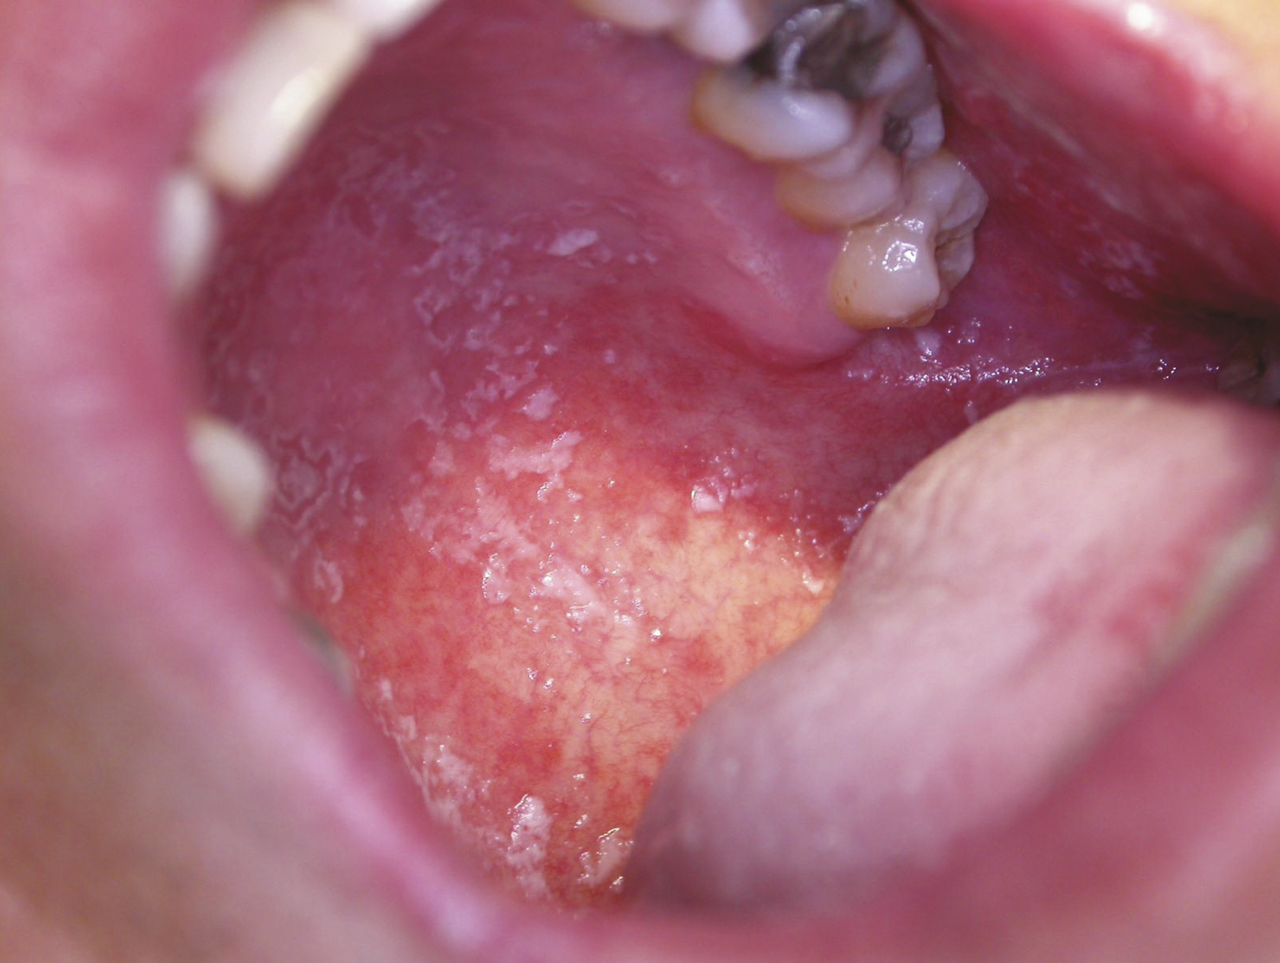

Les stomatites mycosiques sont le plus souvent dues à Candida albicans, levure saprophyte du tube digestif, de la peau et des muqueuses ; l’infection est opportuniste à la faveur d’une modification du terrain entraînant un déficit immunitaire local : diabète, endocrinopathie, hémopathie maligne, infection par le VIH, déficit immunitaire transitoire ou permanent ; traitement médical (antibiothérapie, corticothérapie systémique ou locale avec les traitements inhalés) ; affection locale (sécheresse buccale, carcinome buccopharyngé, mauvais état dentaire, prothèses dentaires, tabagisme). La mycose aiguë se traduit par une efflorescence d’enduits ou de pseudo-membranes blanchâtres (joues, palais) appelée « muguet », détachables par grattage d’une muqueuse érythémateuse (fig. 9). Les signes fonctionnels sont peu intenses : sécheresse buccale, sensation de cuisson, goût métallique. La glossite losangique médiane traduit une infection chronique par Candida albicans. La lésion siège sur la partie médiane de la face dorsale de la langue, en avant du V lingual ; elle a une surface lisse, rosée ou rouge, plane ou mamelonnée, de forme grossièrement losangique à grand axe antéro- postérieur (fig. 10) avec peu de signes fonctionnels ; une lésion érythémateuse en miroir siège sur le palais. Un prélèvement pour culture mycologique est utile. Le traitement repose sur les antifongiques locaux, amphotéricine B, nystatine en suspensions buvables, miconazole en gel buccal. En cas d’inefficacité ou chez les patients immunodéprimés, un traitement systémique est instauré (fluconazole).